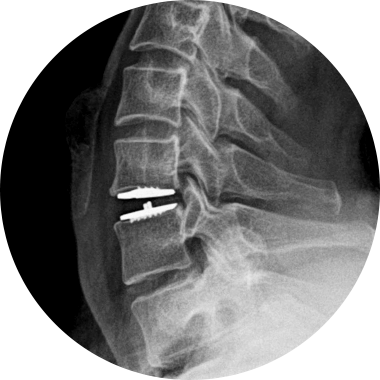

STEP 01

손상된 디스크

STEP 02

손상된 디스크 제거